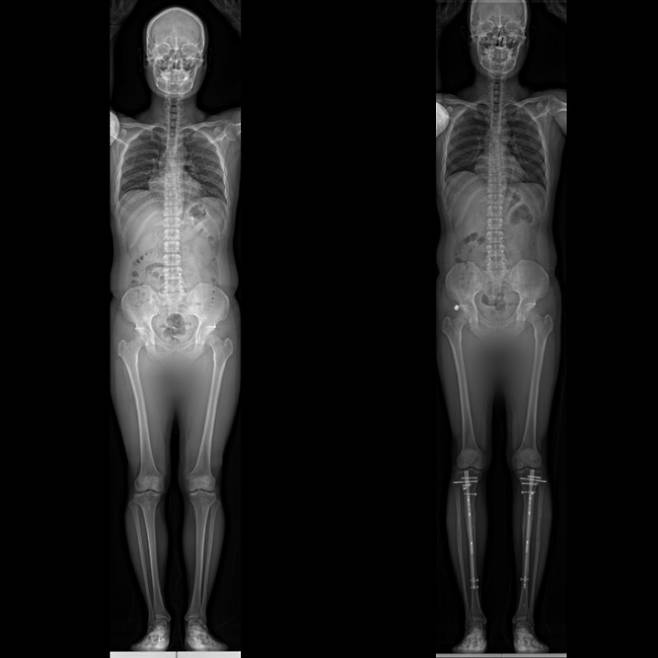

![20대 남성의 종아리와 허벅지 '골 연장수술' 전후 모습. 종아리만 연장하면 평균 6㎝, 종아리와 허벅지를 동시에 연장하면 평균 8~12㎝ 키가 커진다. [이동훈연세정형외과 제공]](https://img1.daumcdn.net/thumb/R658x0.q70/?fname=https://t1.daumcdn.net/news/202202/26/ned/20220226110154286ykex.jpg)

=사지연장술은 어떤 고정장치를 사용하냐에 따라 수술법이 나뉜다. 한국에선 외부·내부 고정장치를 같이 사용하는 하이브리드 방식(LON)을 선호하는데, 종아리만 수술할 경우 평균 6㎝ 연장할 수 있다. 종아리와 허벅지를 동시에 연장할 경우 키가 8~12㎝ 커진다.